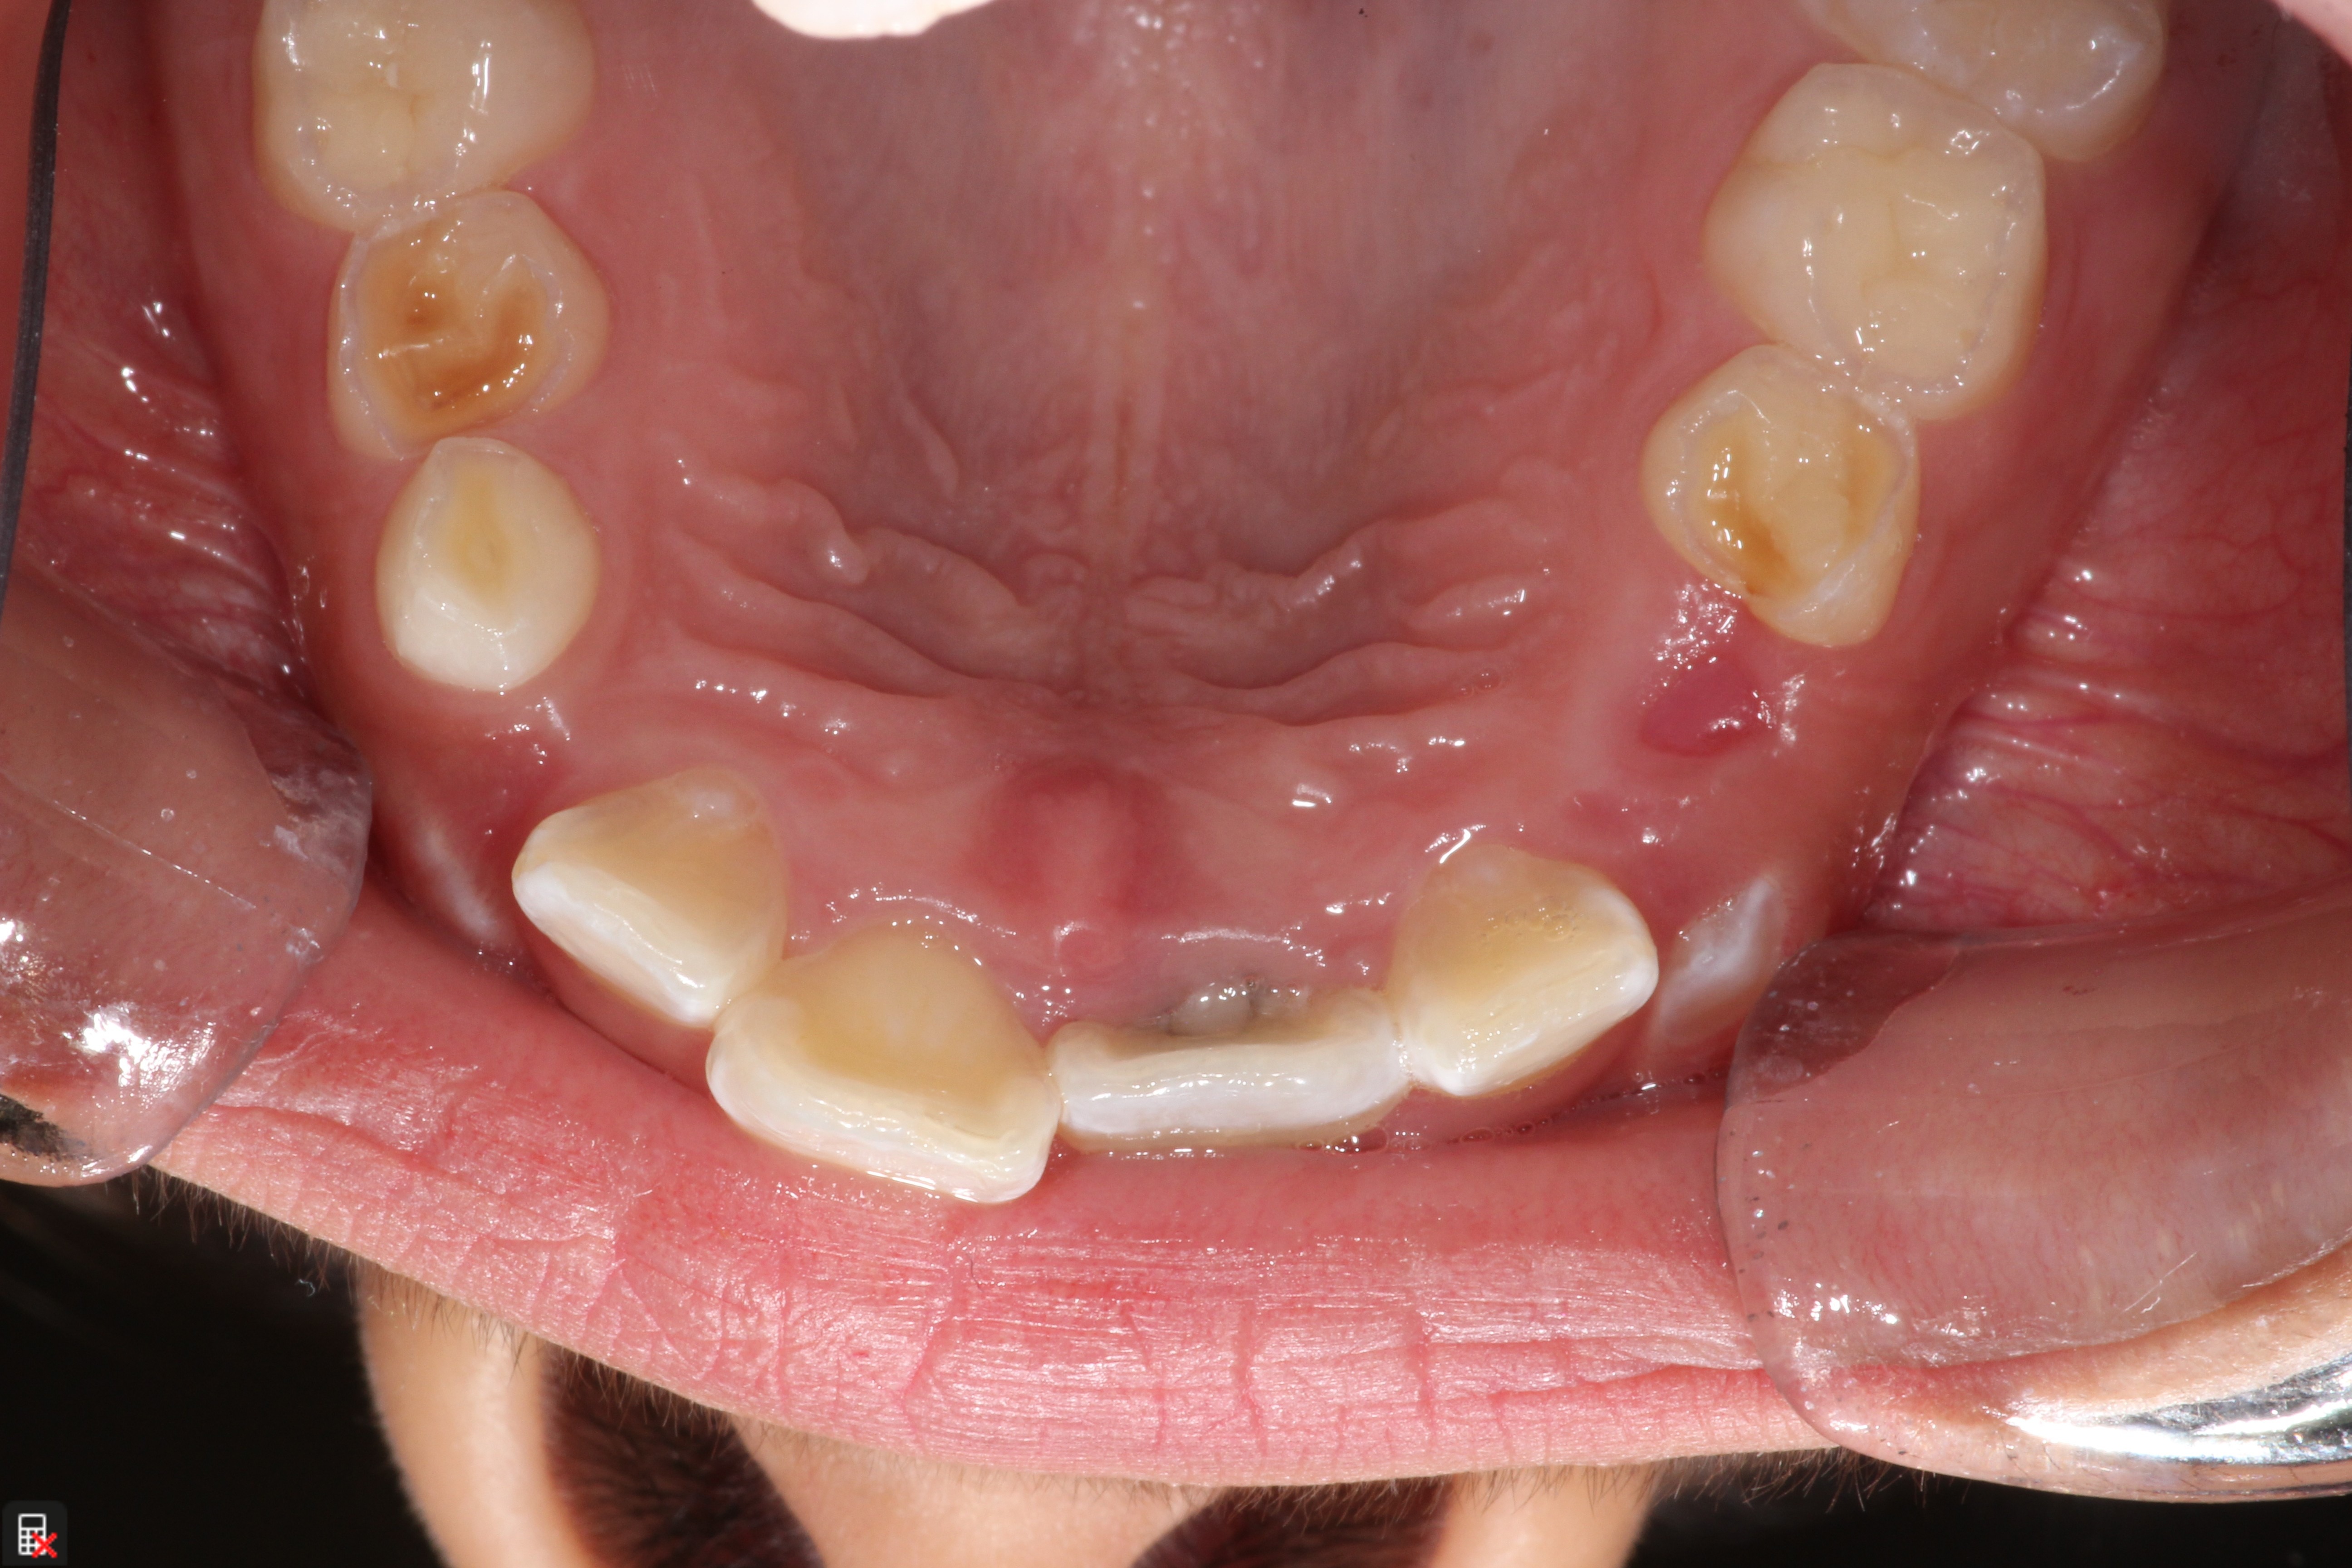

This is a 9yo girl with a high esthetic desire (wants to be a model/actor). She avulsed tooth #9 about 3 years ago, and she has been under treatment with other endodontists. I guess they attempted revascularization with MTA about year ago. #9 is ankylotic with a few mm’s infraposition. It is gray due to the MTA. #8 is slightly yellow/white due to calcification/obliteration but she says she feels cold testing and it is otherwise asymptomatic.

I spoke to her about the following options for #9:

1) Decoronation and a fake tooth for her teenage years

2) No treatment, except internal bleach then bonding/veneer.

3) Autotransplantation of a mandibular premolar

4) Segmental osteotomy/corticotomy later

Are they any other options available? How would you approach this case? Thanks in advance!